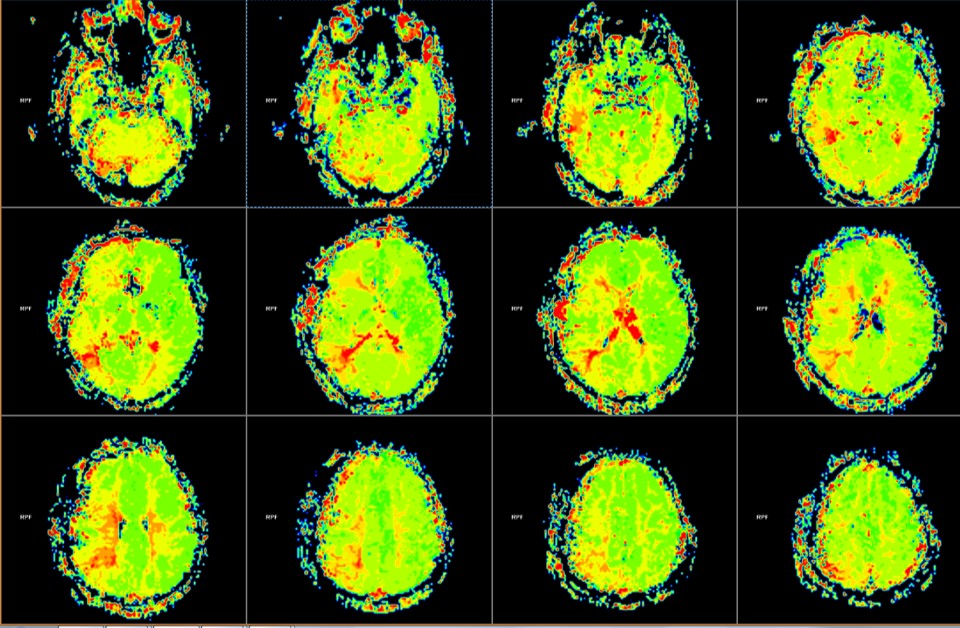

PWI显示:右侧颞叶、额叶下部、半卵圆区、顶叶PTT延长。

术后1周MRI PWI显示:右侧颞叶、半卵圆区、顶下小叶MTT较术前改善。

PWI显示:右侧颞叶、额叶下部、半卵圆区、顶叶PTT延长范围较术前缩小。